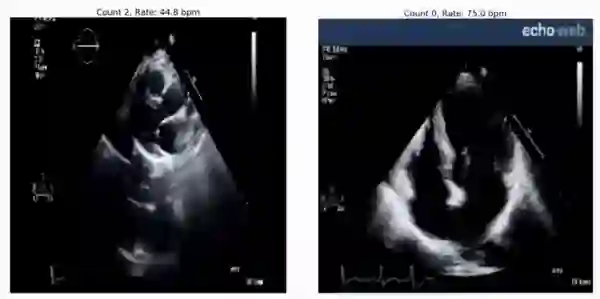

RepNet 可用于评估来自超声心动图的心跳节律,即便其在训练期间并未见过这样的视频:

预测得到的心跳速率:45bpm(左边)和 75bpm(右边)真实的心跳速率分别为 46-50 bpm 和 78-79 bpm。RepNet 对来自不同设备的数据的心跳速率预测非常接近该设备实际测得的心跳速率。